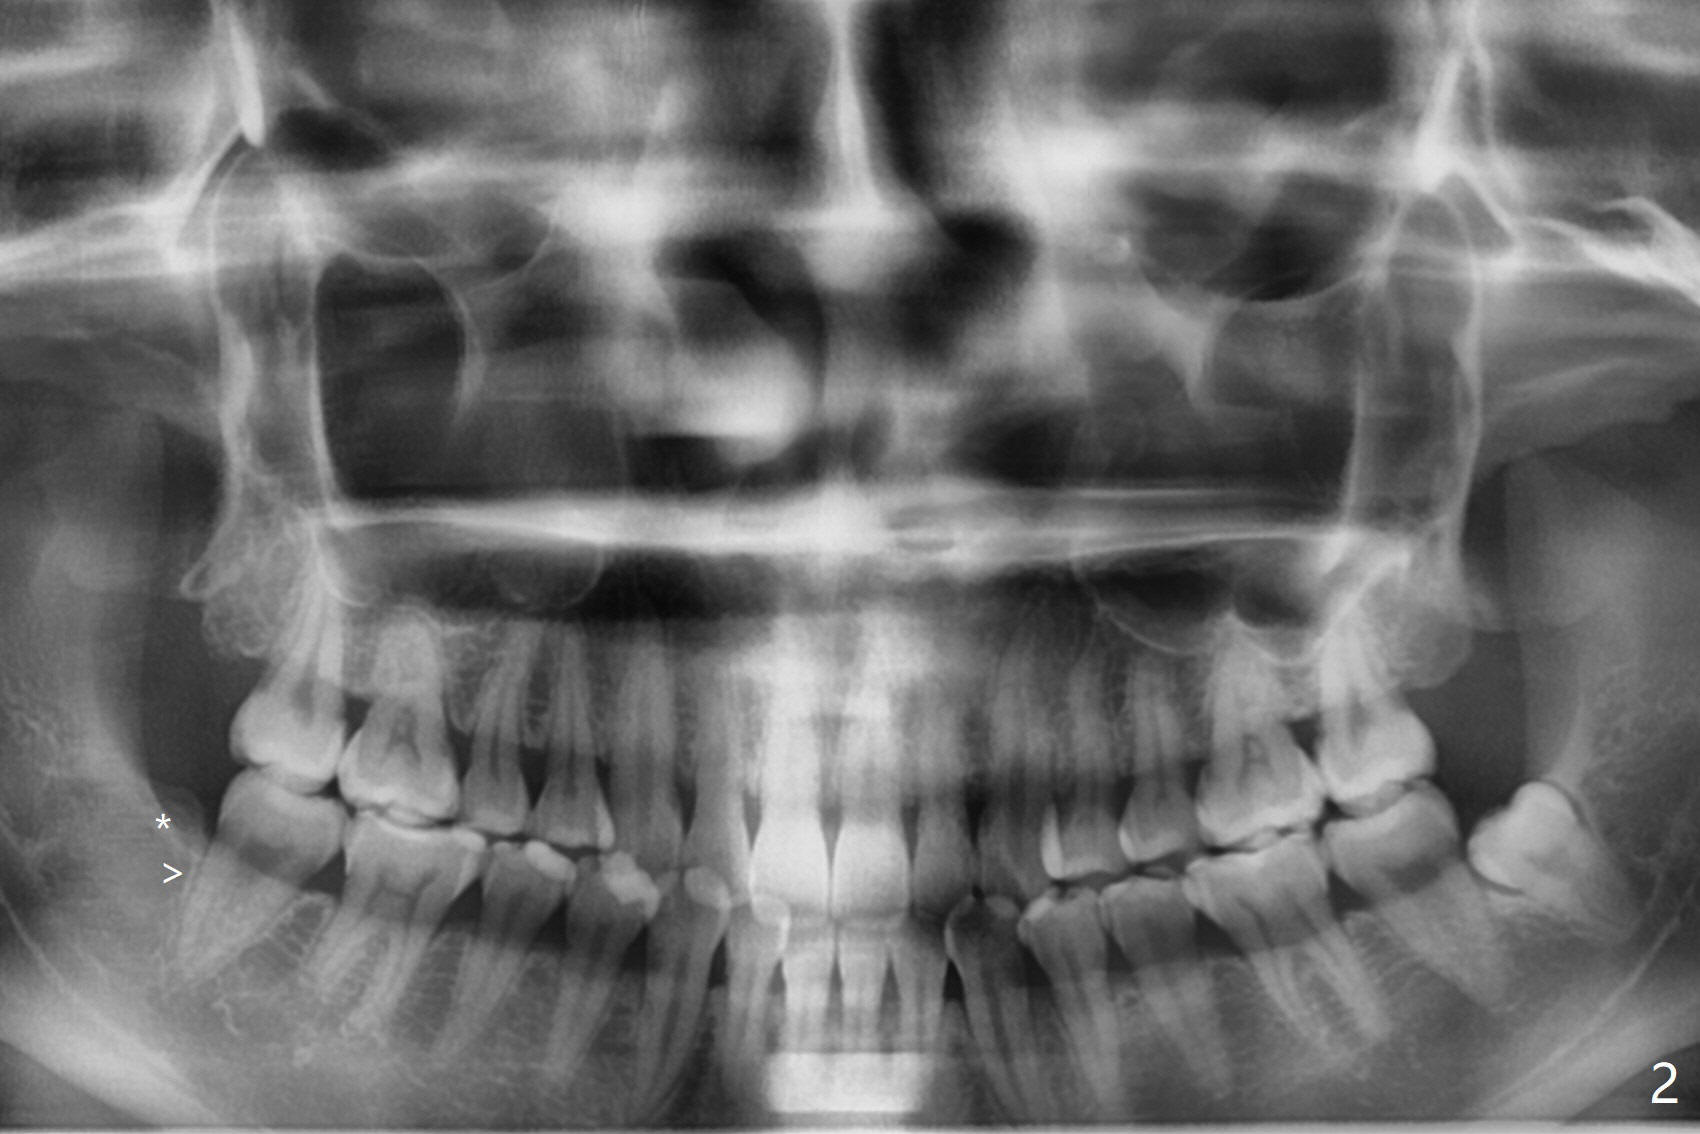

A 34-year-old lady requests extraction of #1, 16 and 32 (Fig.1). After incision for 32, surgical bur is used to create a purchase point to protect the thin bone between #31 and 32. The tooth is extracted with straight elevators and forceps. The socket is large single. Osteogen plug is placed with 4-0 plain gut suture (x4). There is cortical formation in the crest at #1, 16 and 32 three years postop (Fig.2-6 *, arrowheads). The advantage of Osteogen plug over Augma is easy placement with less risk of loss (by dissolving by saliva).